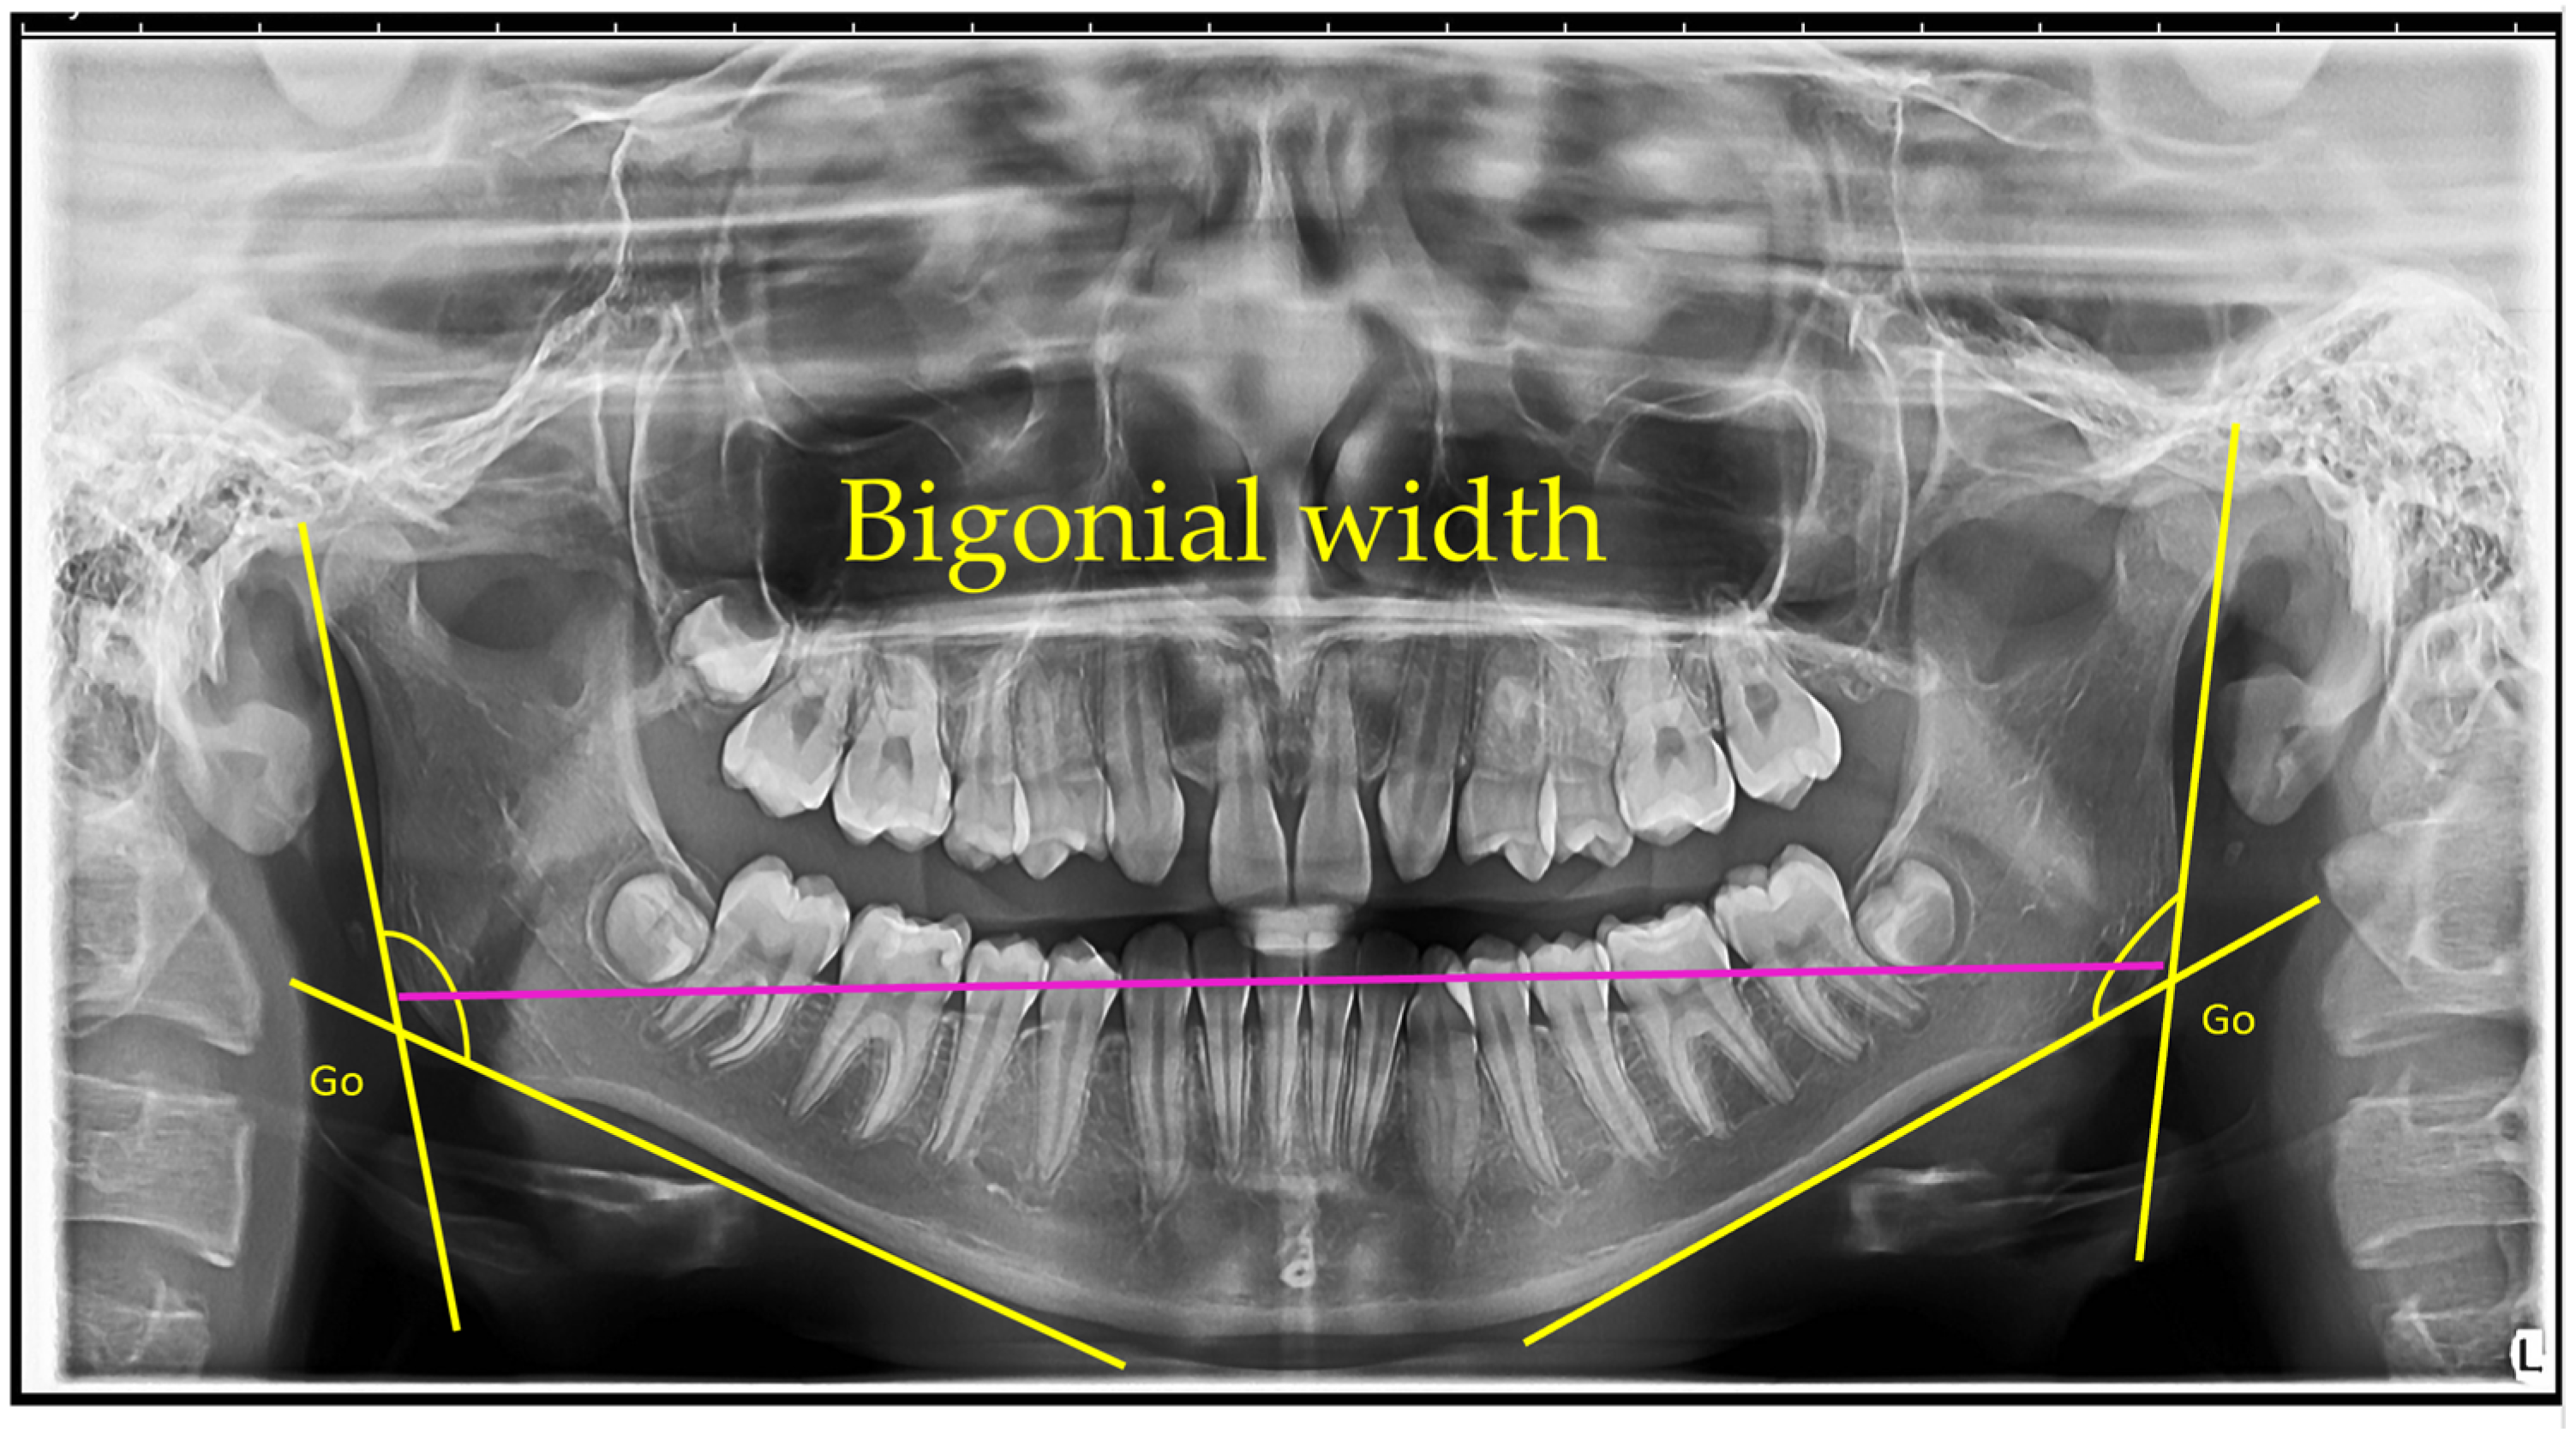

Figure 1, Figure 2, Figure 3, Figure 4, Figure 5 and Figure 6 illustrate the AI-assisted digital measurements exported from the WebCeph software, showing the identification of anatomical landmarks and linear or angular dimensions analyzed in this study.

Orthopantomogram showing the measurement of bigonial width. The gonion (Go) points, located at the most inferior, posterior, and lateral aspects of the mandibular angles on both sides, are identified. The bigonial width is determined as the linear horizontal distance between the left and right gonion landmarks, indicated by the magenta line. Yellow lines depict the mandibular borders used to identify the gonion points (Figure 2).

Figure 2. Bigonial Width Measurement on OPG. Go (gonion)—the most posterior, inferior, and lateral point of the mandibular angle. The magenta line connects the bilateral Go points, indicating bigonial width (mm). Note: Images represent direct screenshots exported from the WebCeph AI platform. Landmarks and measurement lines were automatically generated and manually verified by the authors.